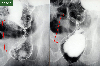

X线

病理学分类恶性上皮性肿瘤/腺癌